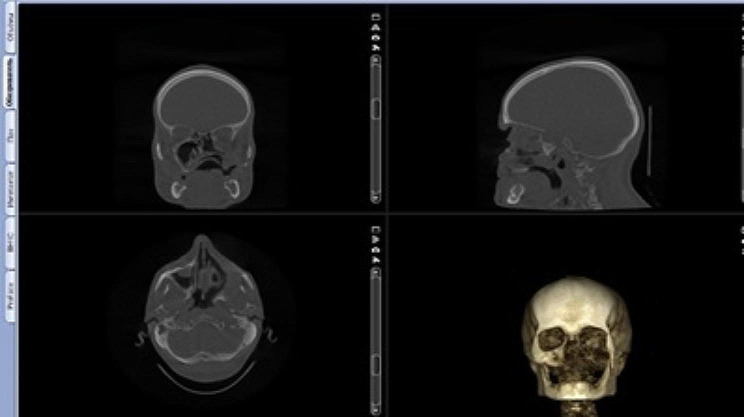

Materials and methods: The study included 16 patients who underwent prosthetic rehabilitation using a zygomatic implant after maxillectomy period from 2021 to 2023. After the tumor was removed, immediate surgical obturators were placed. Main prosthetic rehabilitation was performed 6-12 months after tumor removal, but before that, a temporary obturator was made and used. Six-twelve months after tumor resection, 1-4 zygomatic implants were inserted into the zygomatic bone unilaterally or bilaterally. A total of 42 zygomatic implants were installed, 2 of which were unsuccessful and were removed in 1 patient. The implants were placed using the surgical guide, which was planned and prepared digitally.